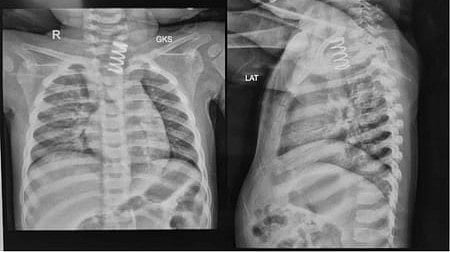

"An X-ray examination revealed a shocking finding -- a large metallic spring was lodged in the upper part of the oesophagus," Dr Jain said.

In the operating room, endoscopy confirmed that the spring had partially embedded itself into the oesophagal wall, with ulcerations extending along the mucosa.